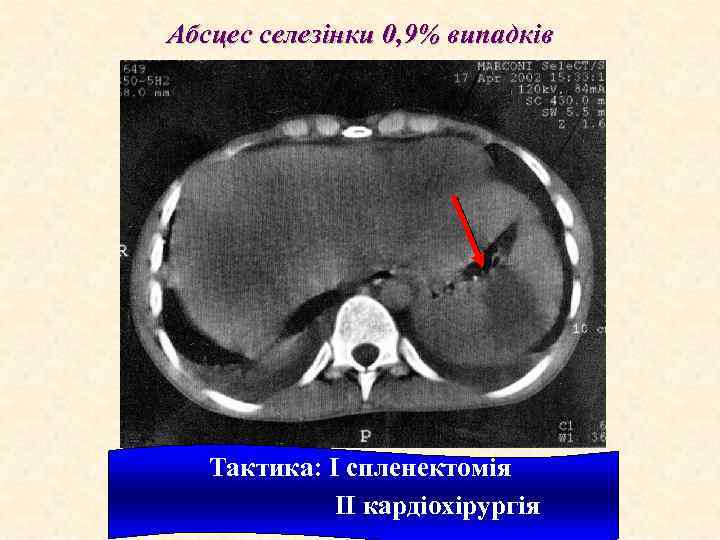

Абсцес селезінки 0, 9% випадків Тактика: I спленектомія II кардіохірургія

European Society of Cardiology ЕНДОКАРДИТИ Ускладнення ІЕ 1. Серцеві ускладнення: а) застійна серцева недостатність; b) абсцеси міокарда; с) перикардити з тампонадою серця; d) інфаркт міокарда; е) розриви хорд, папілярних м'язів; f) круговий абсцес аортального (мітрального) клапана; 2. Позасерцеві ускладнення (в тому числі і внаслідок емболій): а) ниркові: інфаркти нирок, гломерулонефрит (фокальний, дифузний), абсцеси, кортикальний некроз, ниркова недостатність; b) неврологічні і психіатричні: мозковий інсульт (емболічний, геморагічний), інтоксикаційна енцефалопатія (головний біль, запаморочення, сплутаність свідомості, дезорієнтація, психози; корсетний больовий парез, мононеврити); с) спленальні: інфаркт, абсцес, розрив; d) мікотичні аневризми; е) легеневі емболії, інфаркти, пневмонії, абсцеси